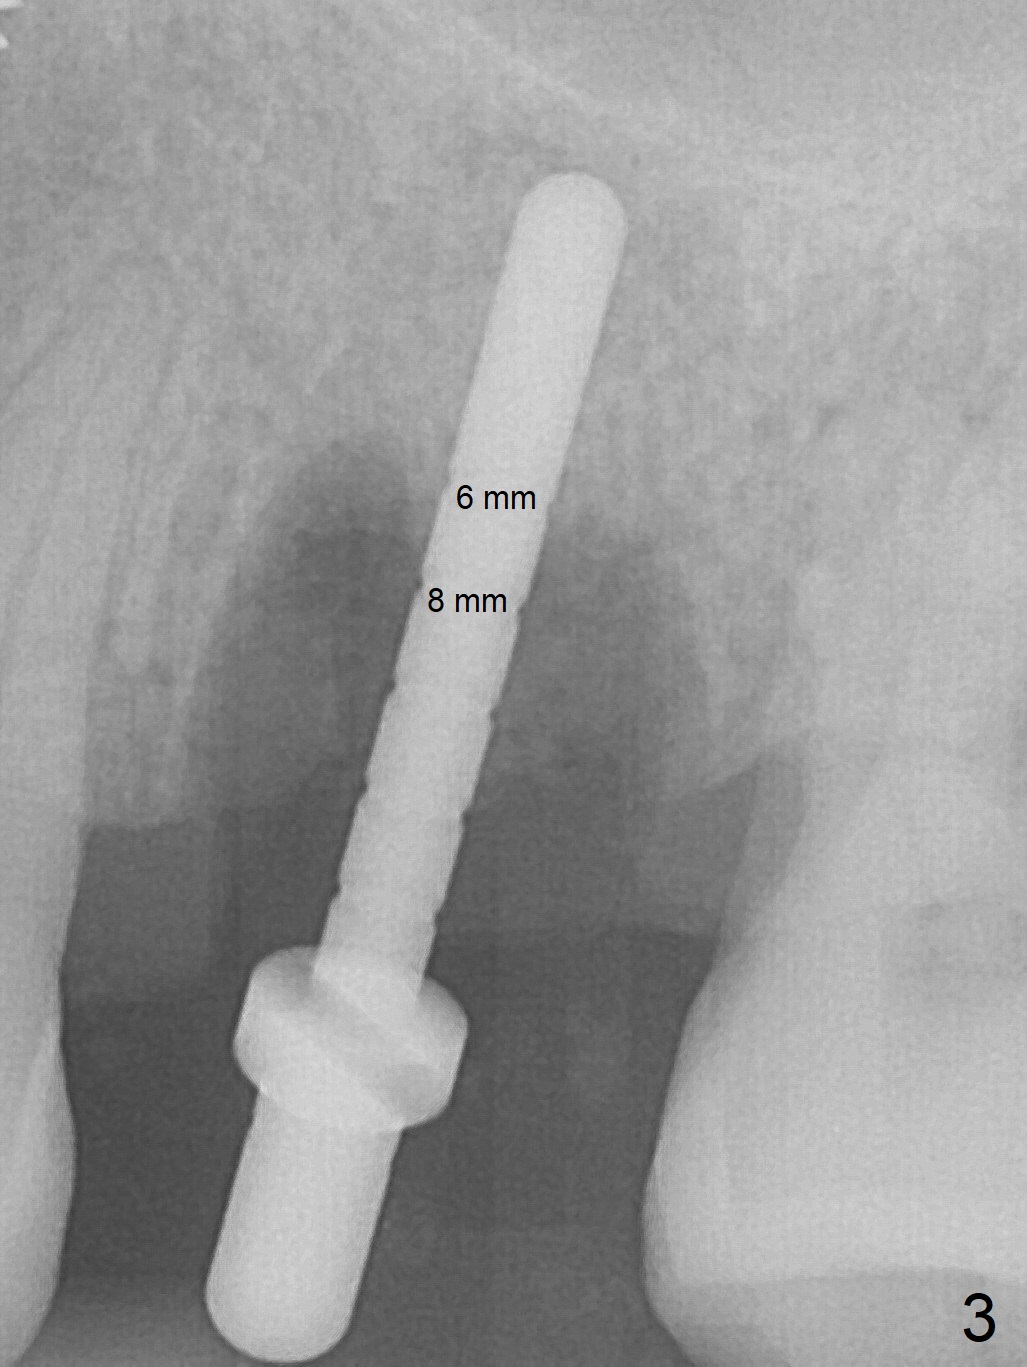

The ridge over the mobile tooth #14 is wide, suggesting bruxism pathogenesis (Fig.1). In spite of calculus over the roots of the extracted tooth (Fig.2), the septum remains. Osteotomy is initiated in the palatal slope of the septum (Fig.3,3' red dashed line). A 4.3 mm Magic Drill (MD) cannot bite into the bone probably because of the slope. Sequential osteotomy has to be done, starting with the smallest MD until 4.8 mm one. A 5x9 mm dummy implant is placed with 50 Ncm (Fig.4). To place 5x11 mm IBS implant (Fig.5), 5.3 mm MD has to be used; prior to implant placement, sinus lift is accomplished with mixture of autogenous bone and Vanilla graft (white *); more allograft (black *) is placed around the implant before insertion of a 6x5.7(3) mm abutment. More allograft is placed around the abutment (Fig.6 *) prior to an immediate provisional fabrication. The grafted bone appears to become the native bone, although at the low density, 6.5 months postop (Fig.7). The implant at #14 appears to have been placed in the middle of the alveolus buccopalatally (Fig.8).